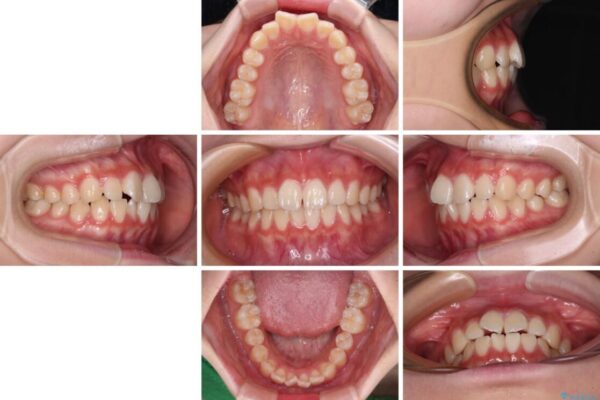

上下前歯のねじれを気にして来院された患者様です。

ワイヤー矯正でもマウスピース矯正でも対応可能でしたが、マウスピース矯正の自己管理が面倒であること、上顎前歯の捻転が著しいことから、ワイヤー矯正での治療を希望されました。

治療前

• インビザラインは使える自信がない ワイヤー装置にて矯正治療 治療前画像